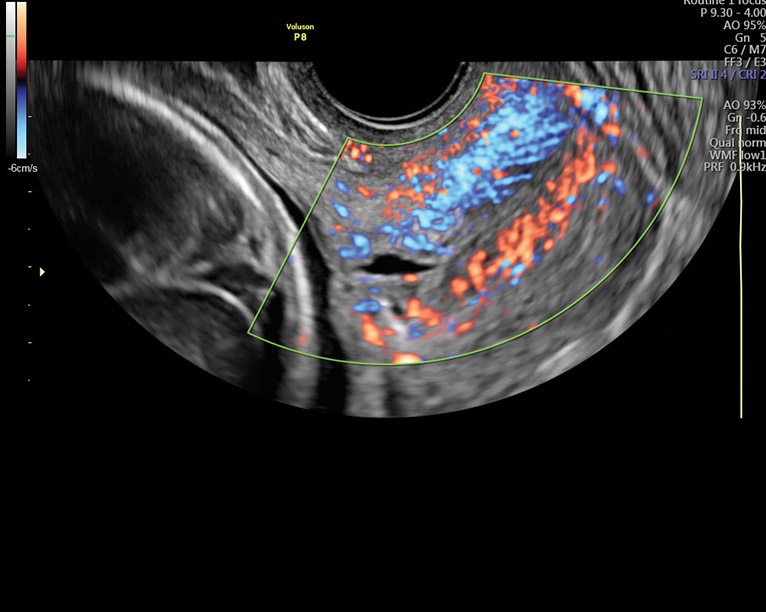

• Усовершенствованное цветовое доплеровское картирование: Эта функция позволяет получить более детальное изображение сердечно-сосудистой системы и ее функциональных систем. Она выводит обследование на новый уровень, обеспечивая более точную визуализацию и анализ данных.

Направленный энергетический допплер:

Да

Энергетический допплер:

Цветовой допплер:

• Работа в В-, М-режимах, наличие импульсно-волнового, цветного допплеровского картирования, тканевого, энергетического и высокочувствительного направленного энергетического допплера (HD-Flow), тканевая гармоника

• Высокочувствительный допплер (HD-Flow), многолучевое сложносоставное сканирование (CRI), Speckle Reduction Imaging (SRI), SonoBiometry (автоматическое измерение BPD, AC, HC, HL, FL)